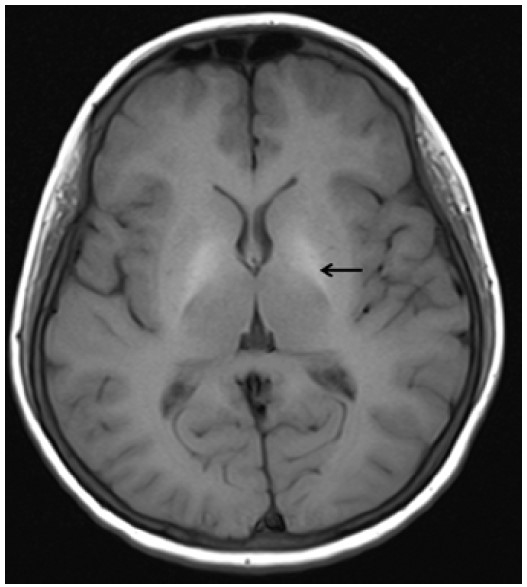

Ультразвуковое исследование органов шеи выявило увеличение размеров щитовидной железы. Ниже левой доли щитовидной железы присутствовало узловое образование (0,8 см) со значительно сниженной эхогенностью [Рис. 1]. МРТ головного мозга продемонстрировала двустороннюю кальцификацию бледного шара с симметричными гиперинтенсивными включениями на Т1- и Т2-взвешенных изображениях [Рис. 2], а также гипоинтенсивность на взвешенных по магнитной восприимчивости изображениях (SWI) [Рис. 3]. Селлярные/супраселлярные поражения либо усиления отсутствовали. Для подтверждения аутоиммунной этиологии мы провели анализ периферической крови пациентки на содержание CD4+FOXP3+Treg клеток, которое составило 2,47 при нормальном значении 6,68, что свидетельствует в пользу аутоиммунной этиологии заболевания.

Рис. 2: Аксиальное Т1-взвешенное изображение головного мозга (время повторения [TR] – 550 мс/ время эхо [TE] – 8,4 мс) на уровне базальных ганглиев демонстрирует двустороннюю симметричную гиперинтенсивность бледного шара.

У данной пациентки наблюдалось сочетание необычных патологических состояний в дополнение к аутоиммунному тиреотоксикозу. У пациентки присутствовала аутоиммунная гемолитическая анемия ‑ известное, хотя и редкое, сопутствующее состояние при болезни Грейвса. Также у неё присутствовала кальцификация глубоких структур серого вещества головного мозга в сочетании с узловым образованием паращитовидной железы на фоне нормального содержания кальция и нормального уровня ПТГ.

Неожиданной находкой в настоящем случае было узловое образование в области предполагаемой локализации паращитовидной железы, ниже левой доли щитовидной железы; образование было выявлено при ультразвуковом обследовании в связи с гиперплазией, аденомой либо инфильтрацией паращитовидной железы. Оно было расположено отдельно от нижнего края щитовидной железы и не являлось экзофитным узловым образованием щитовидной железы. Также было возможно, что узловое образование представляет собой лимфатический узел небольшого размера. Возможность для подтверждения паратиреоидного генеза узлового образования по поглощению сестамиби отсутствовала в связи с недоступностью оборудования для проведения сцинтиграфии паращитовидных желез с сестамиби. Тем не менее, на МРТ пациентки присутствовали признаки кальцификации базальных ганглиев. У пациентки отсутствовали хронические заболевания печени, а также признаки метаболических либо нейродегенеративных расстройств. Наиболее вероятной причиной развития кальцификации базальных ганглиев является эндокринная патология, вызвавшая нарушение метаболизма кальция; данная ситуация может напрямую быть связанной с тиреотоксикозом либо развиваться вторично, на фоне патологии паращитовидной железы [4,5].